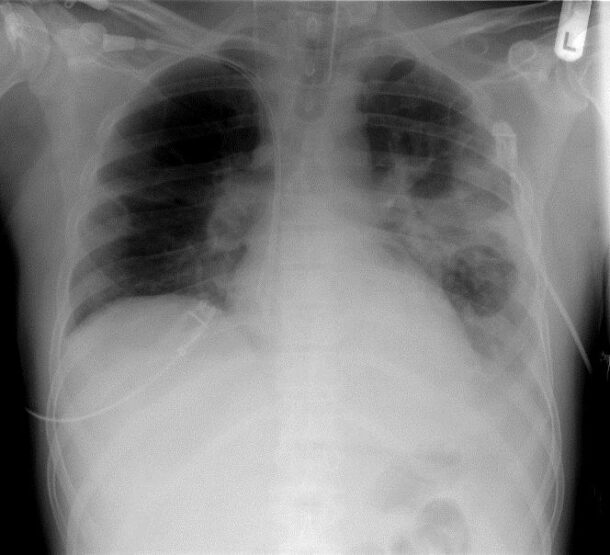

Homöopathie und Lungenentzündung

Homöopathie und Lungenentzuendung

In diesem Jahr habe mir viele Menschen von Pneumonien berichtet. Bei einigen begann es als Grippe, die sich zu einer Lungenentzündung entwickelte, andere berichteten von einem Husten, der immer schlimmer wurde. Dann gab es auch Fälle, in denen ein leichter Husten nicht weggehen wollte und wo schließlich eine Lungenentzündung diagnostiziert wurde.

Eine Lungenentzündung kann viral oder bakteriell bedingt sein. Typischerweise leidet der Betroffene unter Husten mit rostfarbenem Auswurf, Schmerzen in der Brust, Fieber, Schwäche, Schüttelfrost und sogar Übelkeit und Erbrechen. Bei leichteren Formen kann jedoch auch nur ein anhaltender Husten auftreten. Zu den konventionellen Behandlungsansätzen gehören in der Regel Antibiotika, aber seit über 200 Jahren kann auch die Homöopathie diese Fälle erfolgreich, schnell und vollständig heilen.